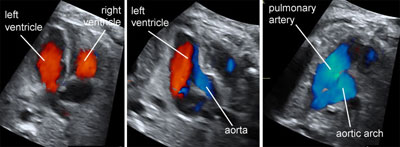

Color Doppler of fetal cardiac connections

Legend:Color Doppler of fetal cardiac connections

The fetal aortic arch

Legend:The fetal aortic arch